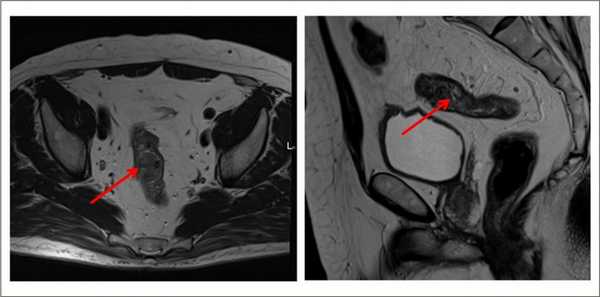

Выявляет даже небольшие по размеру патологические очаги, метастазы и инвазию опухоли в соседние органы, ее топографическое положение относительно других структур. Метод безопасен, не создает радиационную нагрузку, в отличие от КТ.

В диагностике рака анального канала широко используется магнитно-резонансная томография (МРТ). Этот безопасный с точки зрения облучения метод позволяет оценить степень инвазии (распространения) опухоли на окружающие структуры, а также заподозрить наличие метастатических лимфатических узлов.

МРТ органов таза. Злокачественная опухоль стенки прямой кишки; выраженное мягкотканное утолщение стенки органа с признаками инфильтративного роста